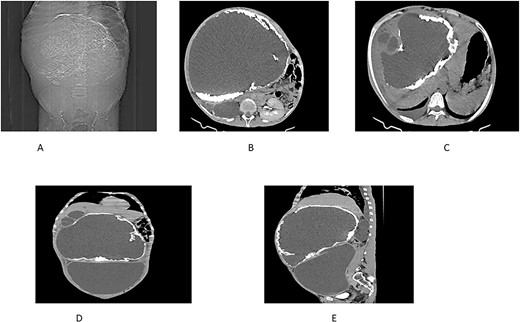

On examination, the patient appeared chronically ill. His vital signs were in normal range except for tachypnea of 48 breaths per minute. Chest examination revealed decreased air entry over the lower posterior one-third of the right lung field. Abdominal examination revealed a grossly distended abdomen (Fig. 1) with a palpable, firm, and non-tender mass measuring 20 × 30 cm.

An abdominal ultrasound revealed a large multicystic intra-abdominal mass with peripheral calcification, displacing the liver superiorly as well as the spleen and bowel loops anterolaterally. Additionally, another hypoechoic mass measuring 2 × 1.5 cm with peripheral enhancement was identified in segment VI of the liver.

An abdominal CT scan demonstrated a massive non-enhancing cystic mass with a thick rim of peripheral calcification, measuring 21 × 28 cm, containing peripherally located daughter cysts and pushing the gallbladder anteriorly. Another well-defined, thin-walled, large peritoneal cystic mass, and measuring 13 × 24 × 28 cm, was observed. This mass exhibited fluid attenuation and a focal anteroposterior wall defect, closely apposed to the hepatic cystic mass. It displaced bowel loops, great vessels, and the right kidney posteroinferiorly while mediating the pancreas.

Further findings included pericalyceal dilatation of the right kidney with an atrophied and thinned-out cortex. Additionally, there was a fluid-attenuating collection measuring ~2.3 cm in depth within the right pleural cavity (Fig. 2).

(A) Scout view showing a large intra-abdominal mass with peripheral calcification. (B) Axial view highlighting a hepatic cyst and an atrophied right kidney with a thinned-out cortex. (C) Axial view depicting a right pleural fluid collection, a hepatic cyst, and two active daughter cysts. (D, E) Coronal and sagittal views depicting the hepatic cyst and the peritoneal cyst (white cross).